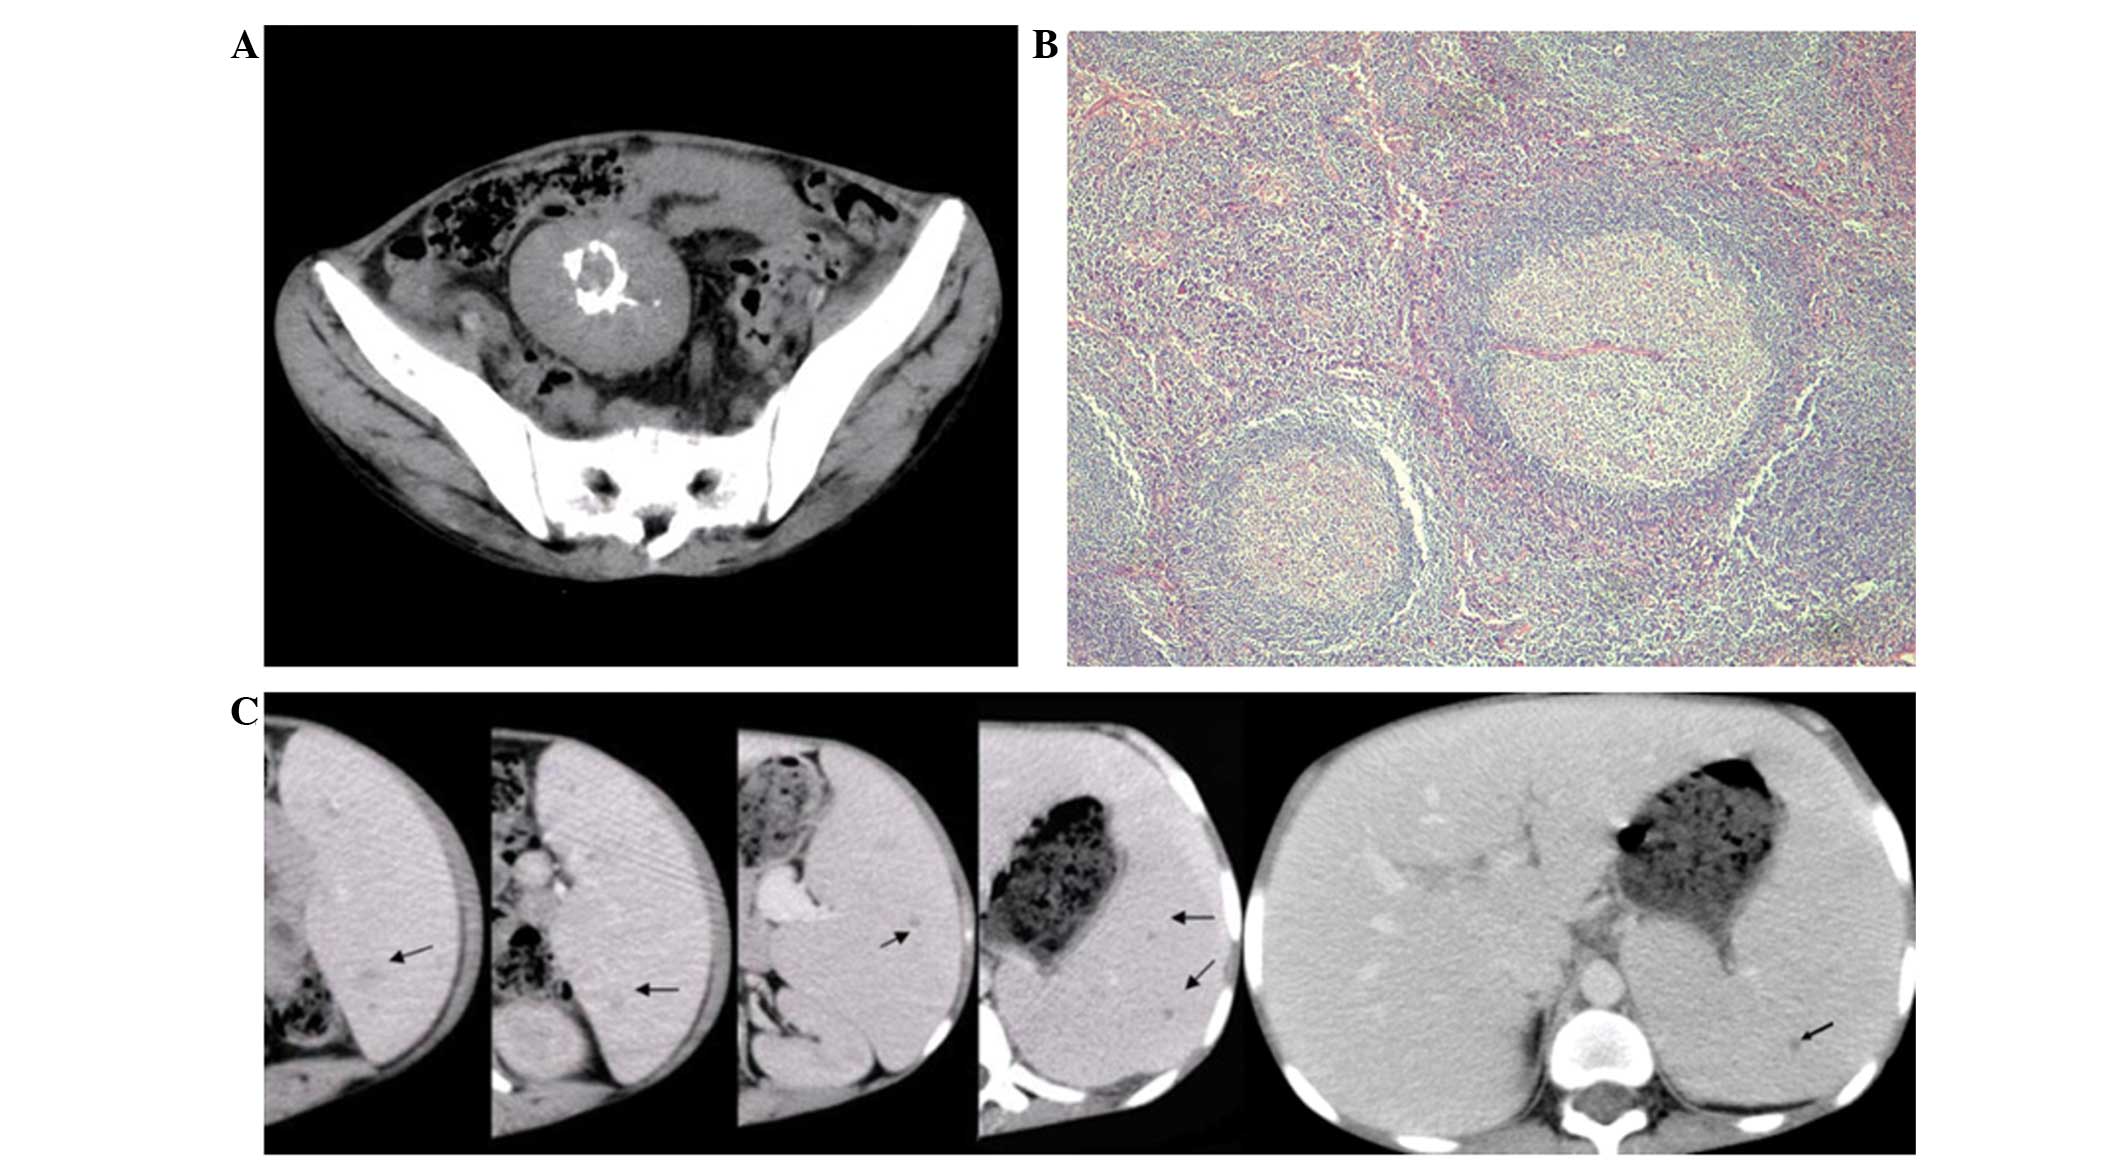

Figure 1

(A) A well-demarcated, moderately enhanced mass with ring-shaped calcification in the center was detected in the mesentery. (B) Hematoxylin and eosin-stained section of the mesentery mass showed involuting germinal center surrounded by concentric rings of small lymphocytes penetrated by hyalinized vessel (original magnification, ×200). (C) Enhanced abdominal computed scan on portal venous phase showed hepatomegaly and splenomegaly with scattered small low-attenuated lesions (arrows showing the lesions of littoral cell angioma in the spleen).

Laboratory test results indicated microcytic hypochromic anemia [hemoglobin, 14 g/l (normal range, 110–150 g/l); hematocrit, 7% (normal range, 35–45%); and mean corpuscular volume, 70.0 fl (normal range, 80–98 fl)], and thrombocytosis (396×109/l; normal range, 100–300×109/l), however, leukocyte count and hemoglobin electrophoresis were normal. A bone marrow smear revealed increased erythrocytic series (41%; normal range, 20–25%) and decreased granulocytic series (46.5%; normal range, 50–60%). Hormone, tumor marker, hepatic and renal function test results were all within normal ranges. An infantile uterus and a solid mass with central calcification were detected by pelvic ultrasonic examination. A moderately enhanced, well-defined mass of 4.8×5.6 cm in size was detected at the mesentery on computed tomography (CT) imaging; centrally located ring-shaped calcification could also be observed. In addition, hepatomegaly and splenomegaly were detected. Scattered small hypo-attenuated nodules were identified in the spleen on the arterial and portal venous phases of enhanced CT images, however, these were isoattenuated on normal CT images (Fig. 1A and C). No abnormalities were observed on liver parenchyma, chest or cervical CT imaging.

As the underlying nature of the mass, nodules of the spleen and hepatomegaly could not be determined in this patient, exploratory laparotomy was performed to remove the mass and spleen, with additional liver biopsy. Subsequent histopathological analysis of the mass was consistent with hyaline-vascular CD, revealing involuting germinal centers surrounded by concentric rings of small lymphocytes penetrated by hyalinized vessels (Fig. 1B). Immunohistochemically, the mass was reactive for CD3±, CD20±, bcl-2 (+) and Ki-67. In addition, pathological and immunohistochemical examination of the spleen showed a hybrid endothelial-histiocytic phenotype, which confirmed a diagnosis of littoral-cell angioma. Fatty degeneration was identified in the specimen of the liver. Following surgery, the patient’s symptoms resolved and laboratory tests normalized. Follow-up was performed once a month, and menstruation and breast development commenced three months following the surgery. At the time of writing, no recurrence had been identified.